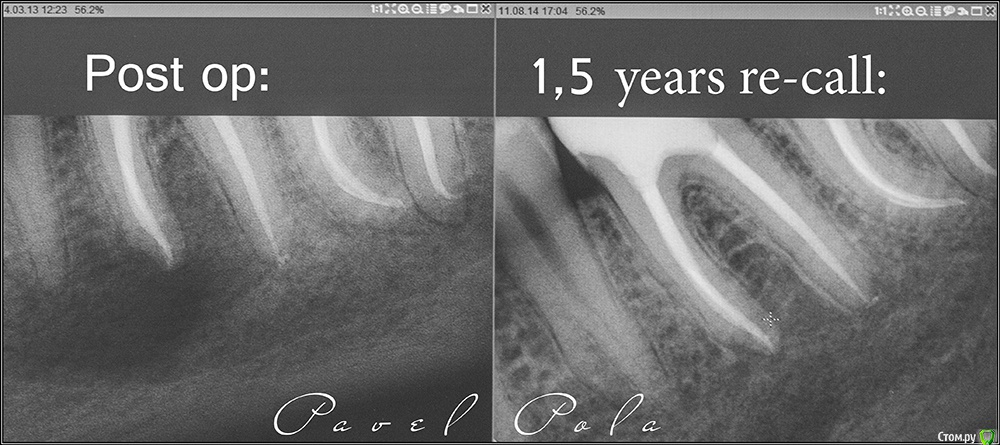

Ксения_ Опубликовано 27 августа, 2015 Поделиться Опубликовано 27 августа, 2015 (изменено) Здравствуйте Уважаемые Доктора! КТ сделано 4 мес назад. После этого пролечен кариес 14, 16, 37, 35. Пролечен пульпит 25, 36.Осталось пролечить пульпит в 15, 26, 47. Удалить все восьмерки.Далее ортодонтия. Стоит вопрос об удалении 46. Зуб ранее был пролечен другим врачом некачественно (+ пропущен канал).Мой лечащий доктор, после консультаций с коллегами, предлагает удаление, т.к. с его слов прогноз у этого зуба неблагоприятный (считает, что через пару лет процесс повторится) и смысла в столь дорогом лечении нет. Мне, конечно, хотелось бы по возможности зуб сохранить.Как вы считаете какой прогноз у этого зуба? P.S. Зуб не беспокоит. Точнее ни один зуб у меня вообще ни разу в жизни не болел (несмотря на такое количество пульпитов, которые для меня были неожиданностью. Врачу своему доверяю.). Несколько докторов которые меня смотрели считают, что у меня высокий болевой порог. Изменено 27 августа, 2015 пользователем Ксения_ Ссылка на комментарий

M@estro Опубликовано 27 августа, 2015 Поделиться Опубликовано 27 августа, 2015 (изменено) Судя по рентгену - прогноз благоприятный. Зуб сохранен,это главное. "процесс повторится" - на это при современном подходе выделяют не более 5 % .Если бы у меня 95 % вероятности в казино было - я бы дом поставил , не то что зуб полечил ) Ключевое при перелечивании - соблюдение современного протокола лечения. P.s. После лечения уже больше двух лет прошло,недавно был на осмотре - процесс все никак не повторится )) Изменено 27 августа, 2015 пользователем M@estro 3 Ссылка на комментарий